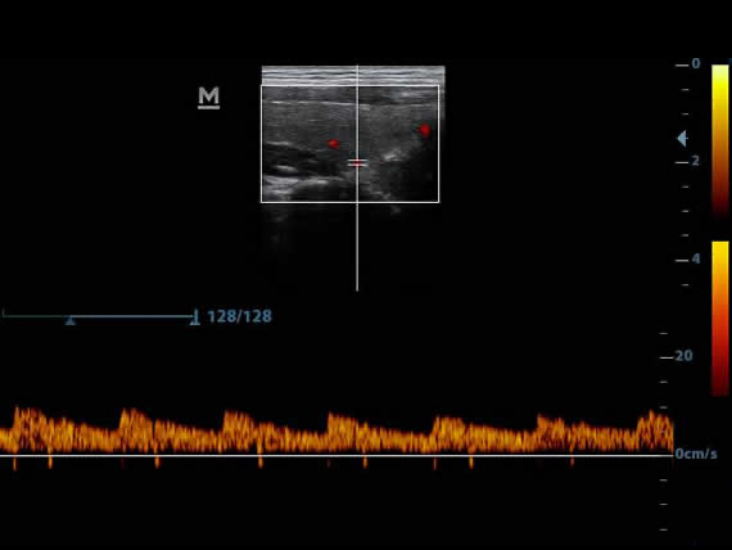

El Power Doppler ayuda a identificar el flujo sanguĂneo en diferentes condiciones clĂnicas; es una forma esencial para localizar los vasos y simplifica su mediciĂłn precisa.

?